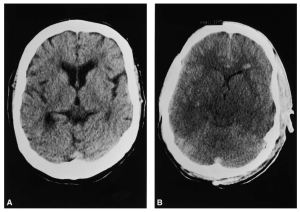

La hiponatremia grave (<125 mmol/L) o de instauración aguda suele acompañarse de clínica derivada del edema cerebral. Cuando la hipoosmolaridad se instaura de forma aguda superando los mecanismos de adaptación, el incremento del tamaño celular inducirá un edema cerebral comprimiendo pequeños vasos y causando isquemia e infartos (Figura 2). Puede comenzar como un cuadro confusional con náuseas y vómitos, desorientación y somnolencia, evolucionando hacia el estupor y el coma con convulsiones y distrés respiratorio. En el peor de los casos se puede llegar a la herniación cerebral con compresión del tronco del encéfalo y la muerte.